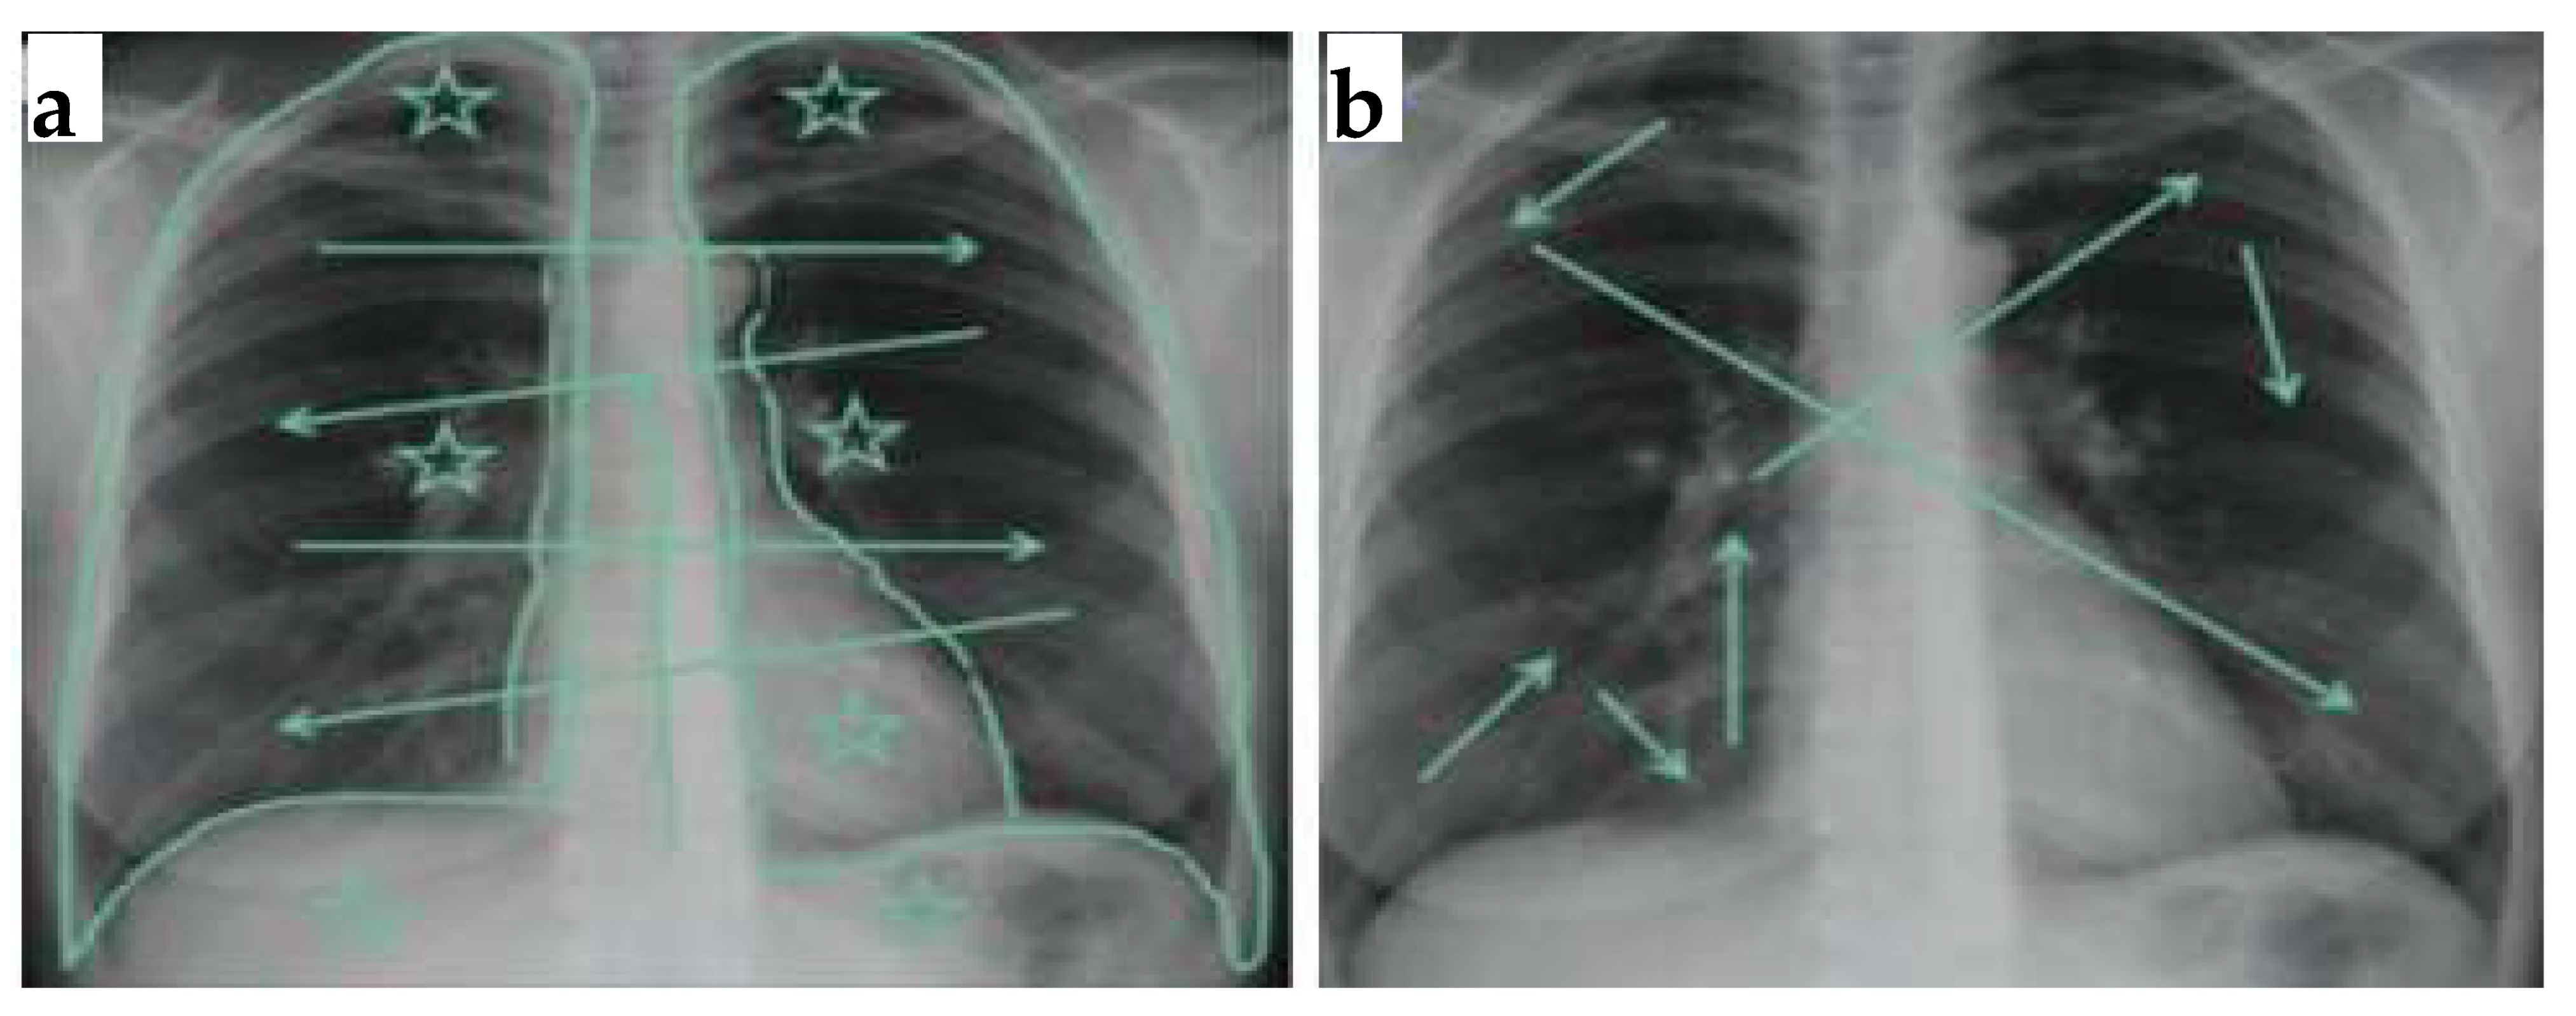

Applied Sciences Free Full Text Lung Nodules Localization And